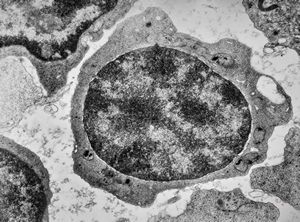

F,51y. | blood - chronic lymphatic leukemia … prolymphocyte